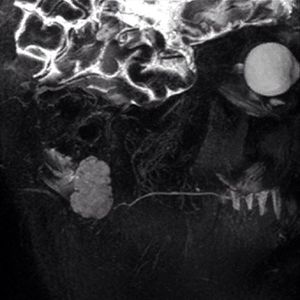

MR sialography is a non-invasive MRI technique used to evaluate diseases of the salivary ducts. MR sialography is based on the principle that stationary fluids will produce bright signal on heavily T2-weighted images. Sialography uses T2 weighted sequences with very long TR (8000) , TE(500) and fat suppression to highlight fluid and suppress other surrounding tissue signals. MR Sialography has the advantage of depicting the glandular parenchyma in addition to depicting sialolithiasis and other changes of the ductal structure. MRI imaging has the potential to provide spatial information on salivary gland function.